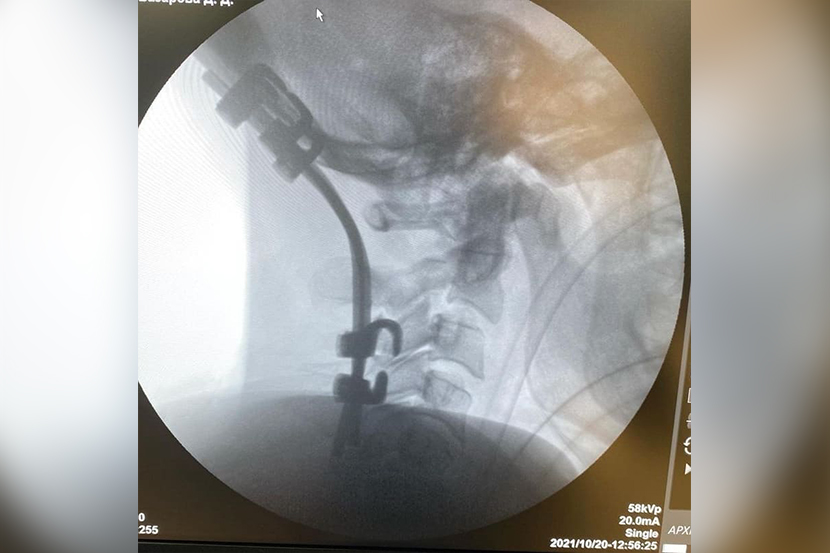

Уникальная операция в Бурятии: события и детали